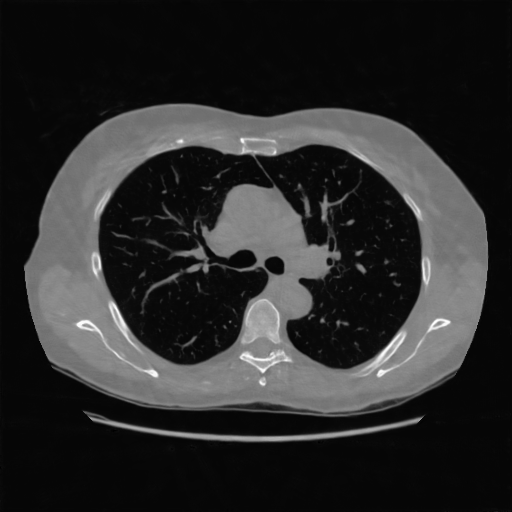

4.3 Few-View CT Reconstruction

In this section, the reconstruction performance of our proposed framework under few-view conditions will be tested. For the parallel-beam and fan-beam geometry, the number of views increases from to , uniformly distributing from to and to respectively. Such settings provide a complete benchmark of reconstruction performance, ranging from extremely sparse to relatively complete, full-view CT reconstruction. The experiment results are shown in Fig.5. Additionally, the ground truth, few-view ( views), and full-view ( views) CT reconstruction results of different methods are shown in the first and third rows of Fig.7 (parallel-beam, LIDC-IDRI dataset), and Fig.8 (fan-beam, LIDC-IDRI dataset).

(a) Ground Truth

(b) 19.01dB

(e) 15.35dB

(c) 37.72dB

(f) 20.54dB

(d) 38.96dB

(g) 22.84dB